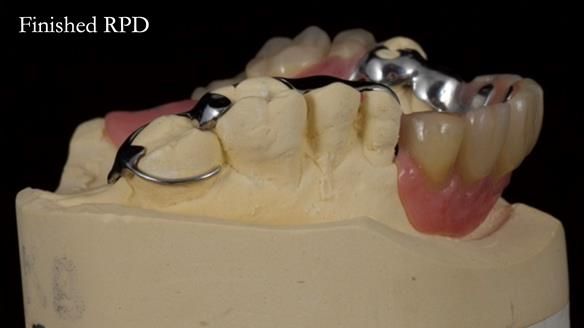

Keith’s case was one of the most challenging and rewarding cases I’ve treated this year. This 64 year old man presented with ill-fitting acrylic partial dentures that lacked stability, retention, and aesthetics. They constantly broke. He had lost the upper front teeth in a road traffic accident in his early 20s. The unopposed teeth had erupted, taking up space. After careful planning, we made a durable, metal-based upper partial denture/splint to address his dental concerns. He loved the outcome.

1. Denture design: A custom cobalt-chromium framework was Scandinavian-designed to maximise stability, protect the remaining teeth, and allow for future additions if needed.

Keith’s denture incorporated a Duracetal shell clasp on upper right first premolar (Myerson), which are designed to be virtually visible, providing a more aesthetic solution while enhancing patient comfort. The Scandinavian-inspired approach, based in modern removable prosthodontic techniques, ensured the denture was not only durable but also visually pleasing. Additionally, the design was carefully planned to allow for future modifications, ensuring that if Keith loses additional teeth, the denture can be adapted rather than replaced entirely.